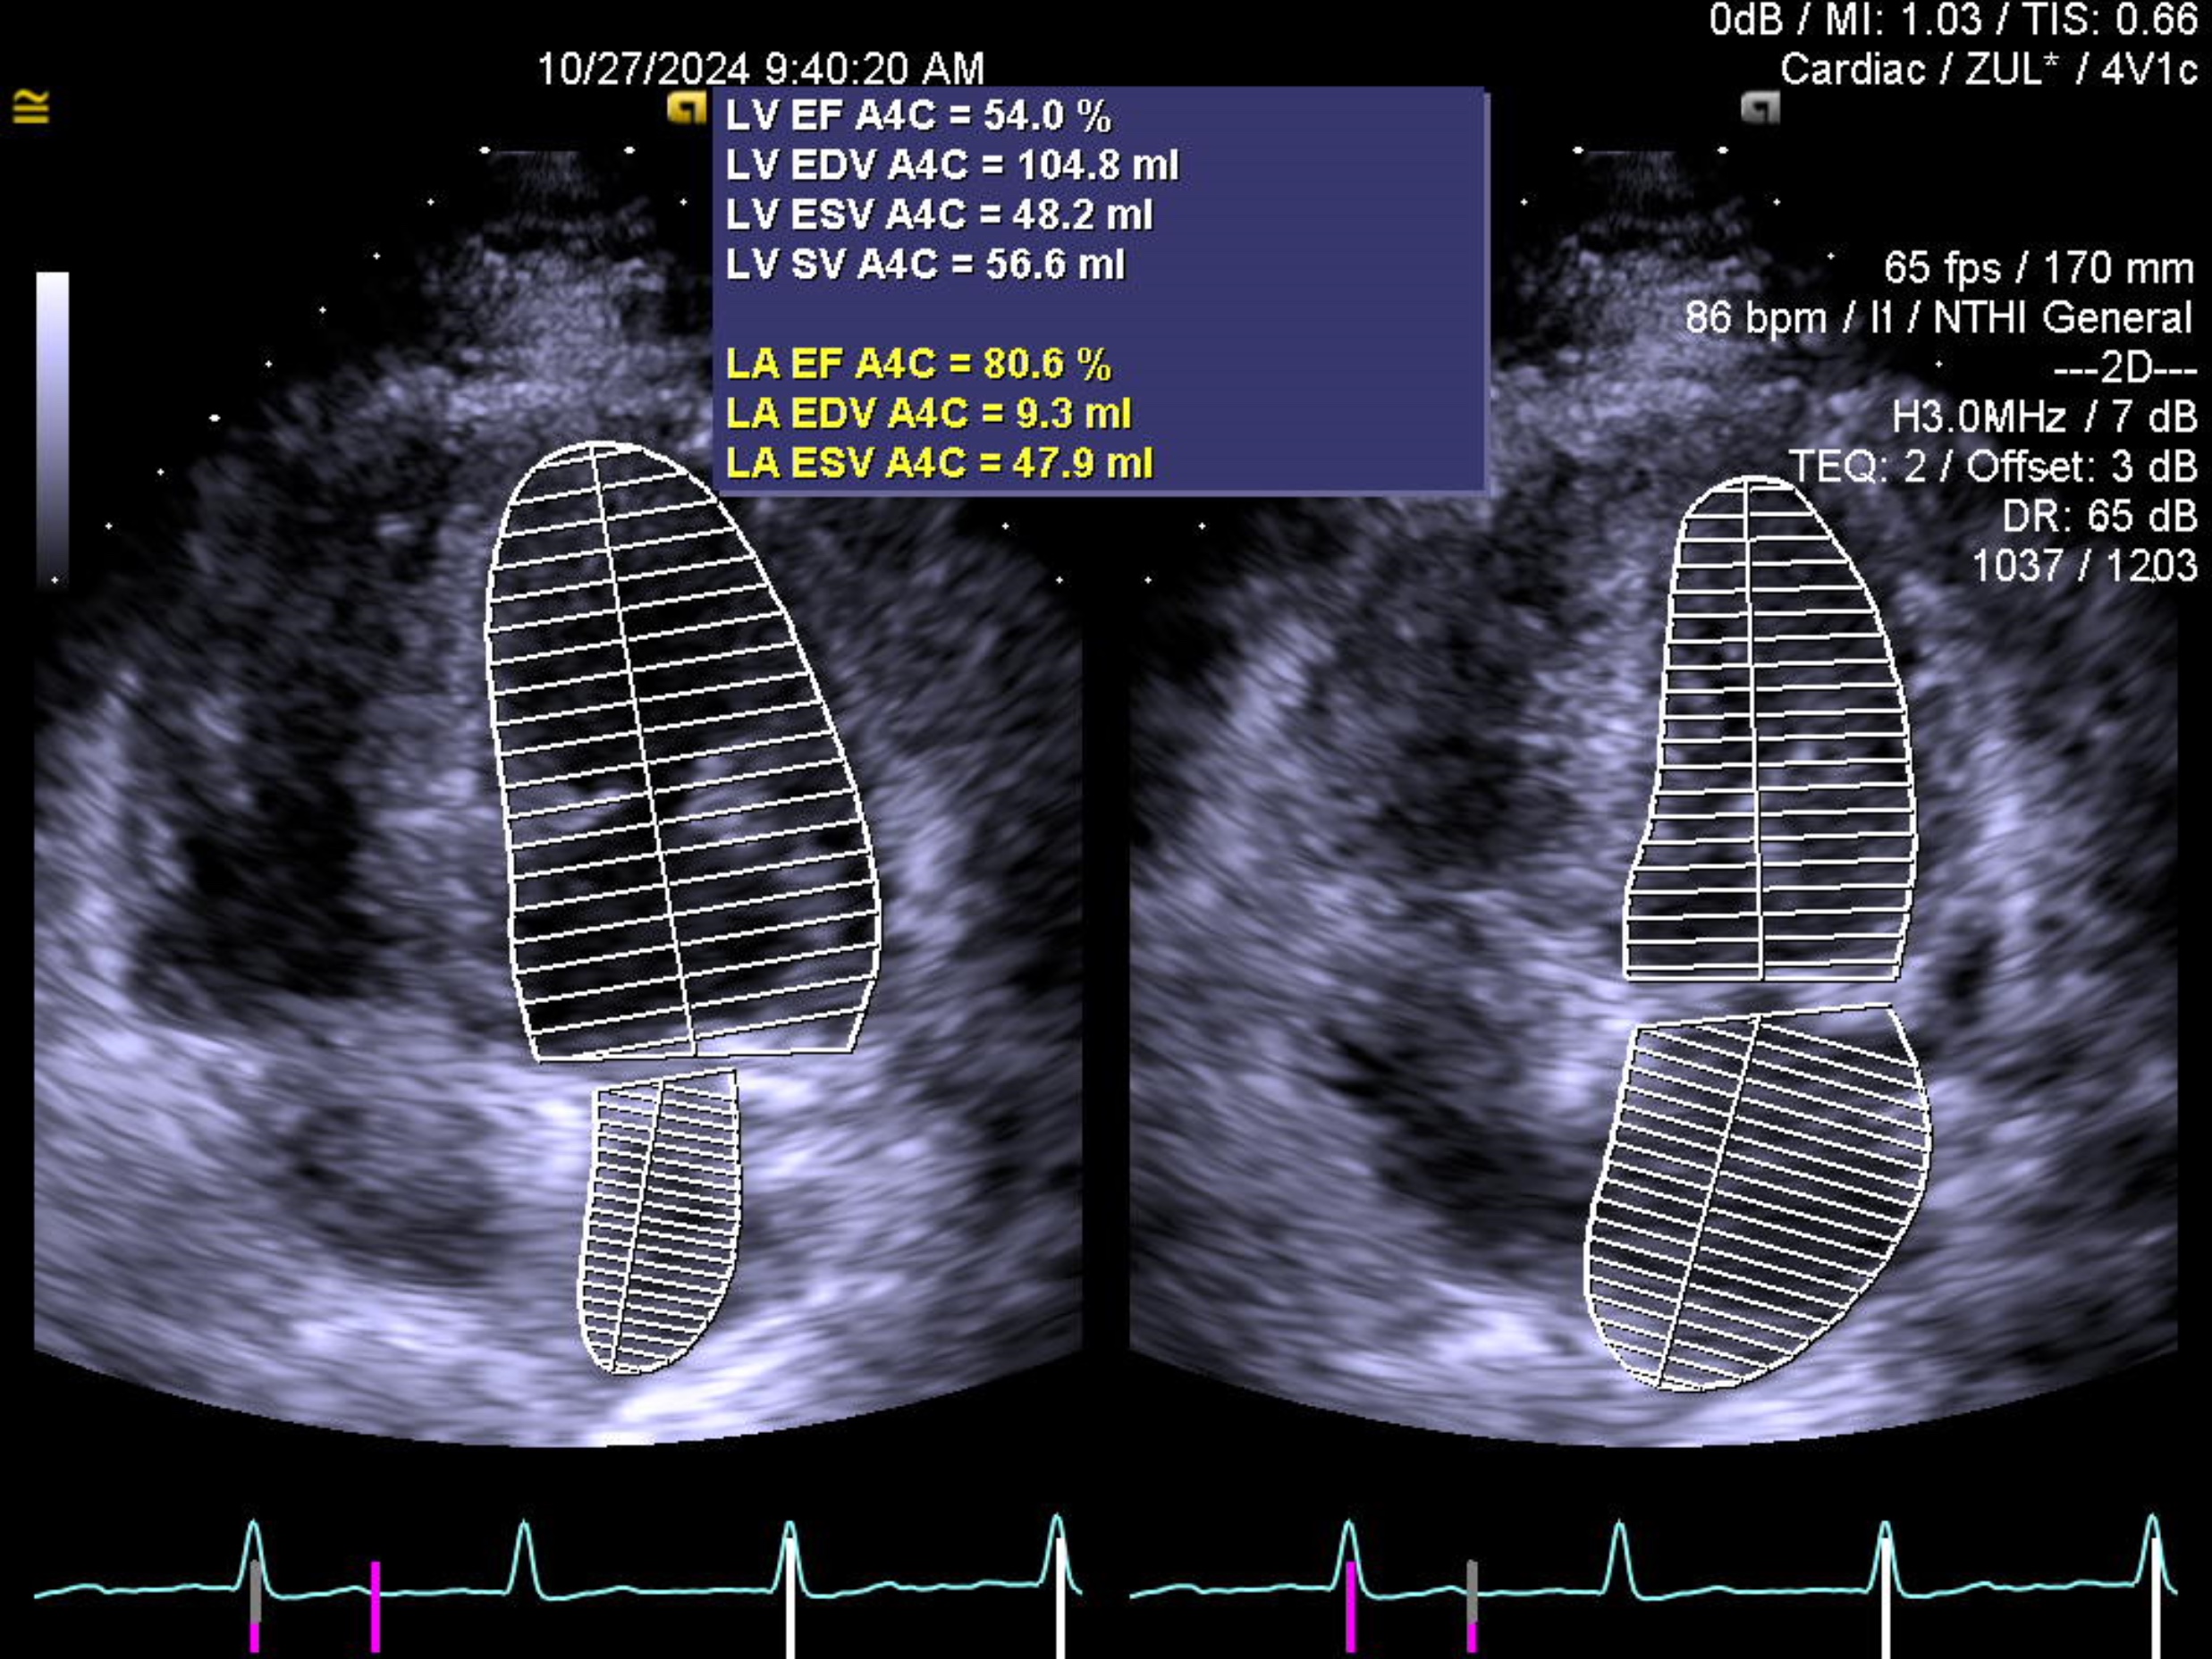

His blood investigations were unremarkable with a normal troponin reading. The electrocardiography shows sinus rhythm with normal axis, absence of left ventricular hypertrophy, Q wave, ST deviation or T wave inversion. The echocardiography showed no regional wall motion abnormality with normal left ventricular ejection fraction. A computed tomography of coronary artery revealed a subtotal occlusion over the left anterior descending artery (LAD).